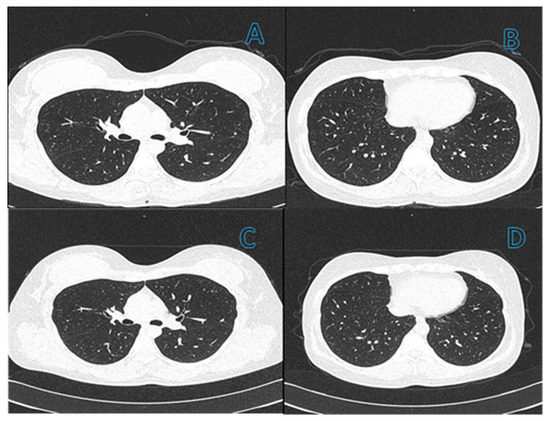

Pulmonary fibrosis was diagnosed in 31/149 (21%) patients based on a combination of tomographic findings, including parenchymal bands, irregular interfaces, a thick reticular pattern, and bronchiectasis confirmed by a pulmonologist. Figure 2 and Figure 3 shows computed tomography scans from patients without (Figure 2) or with (Figure 3) diagnosis of pulmonary fibrosis after a follow-up of six months from initial infection by SARS-CoV-2.

Figure 2.

(A,B) Computed tomography (CT) scans of the chest with 1 mm slices of a 46-year-old female patient in the active phase of infection. CT does not show changes in the lung related to pneumonia. (C,D) Images of CT six months after resolution of SARS-CoV-2 infection have no change from initial CT ones, which discard a history of lung damage.